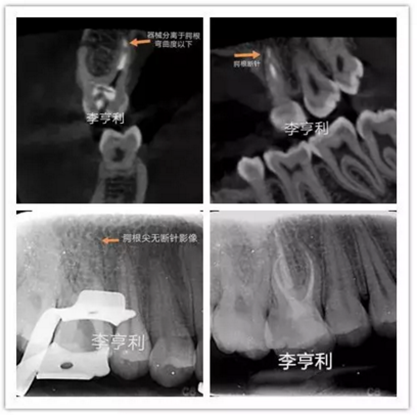

李亨利取出腭尖斷針的病例

在根管治療前,一定要充足地預估難度,謹記根管解剖,并且要熟悉自己臨床使用器械的設計、尺寸和參數(shù)。雖然說斷針本身并不影響治療效果,但往往都是因為患者的個人意愿,最后選擇取出斷針。如果難度超過術者自身的能力,就一定要轉(zhuǎn)診至專科的牙體牙髓醫(yī)生進行處理。